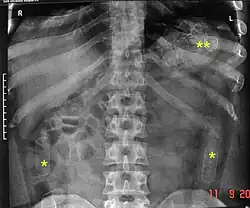

Es besteht ein großes Risiko für das Leben des Bodypackers, wenn eines der Päckchen platzt. Dabei können die giftigen Wirkstoffe der Droge austreten und über die Schleimhäute aufgenommen werden. Der Nachweis der Päckchen geschieht durch eine Röntgenübersichtsaufnahme des Bauchraums und durch Sonografie. In Sonderfällen ist eine endoskopische Bergung möglich. Ein operativer Eingriff, um die Container zu entfernen (Laparotomie), wird bei gerissenen Behältern durchgeführt sowie dann, wenn die Chance des Zerreißens als groß eingeschätzt wird.